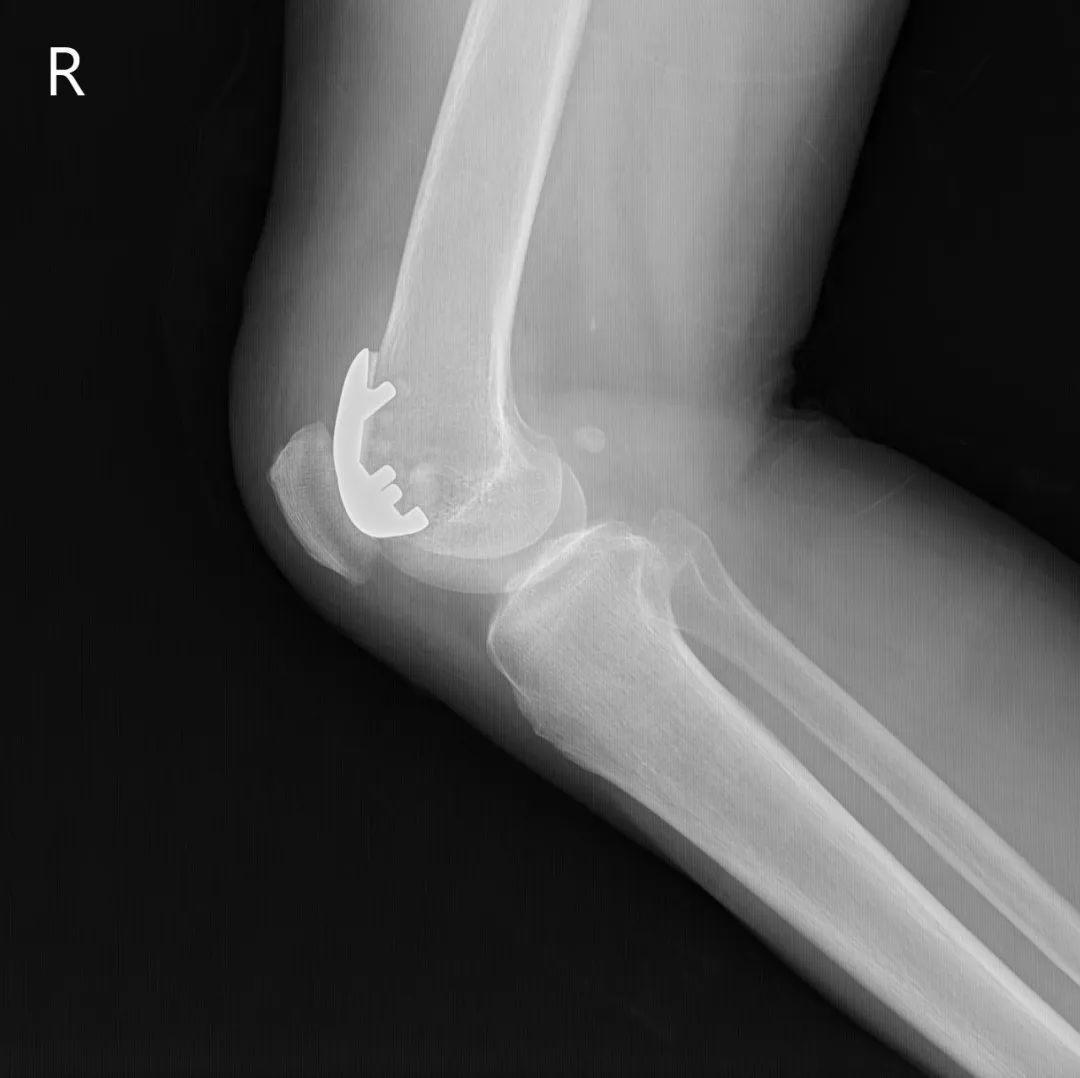

74岁的吕阿姨膝关节疼痛10余年,屈伸活动受限,外院就诊止痛药等保守治疗效果欠佳,拍片提示膝退行性骨关节炎。近日,她慕名来到上海市同济医院骨关节外科中心程飚主任门诊,程飚主任结合患者症状,影像学结果,体格检查,发现吕阿姨主要问题集中在膝关节内侧及髌股关节,膝关节外侧尚可。

为尽可能保留吕阿姨关节,程飚主任对定对吕阿姨进行膝关节部分置换手术,包括膝关节内侧单髁置换,髌股关节表面置换,尽可能减少膝关节截骨量,尽快恢复膝关节功能。吕阿姨术后第一天就开始下地走路了,她表示膝关节疼痛明显缓解,膝关节的活动范围也明显增加了,对程主任精准的手术治疗表示衷心的感谢。

部分膝关节置换手术目前已是非常成熟的治疗方法,亦属于保膝治疗的一种。主要包括单髁置换,髌股关节置换。单髁置换主要把膝关节内侧髁或者外侧髁表面已经磨损的部分替换成金属的假体和高分子聚乙烯耐磨垫片。髌股关节置换主要把髌股关节表面已经磨损的部分替换成金属的假体。

主要为退行性骨关节炎的患者,病变局限于内侧或者外侧胫股关节,可行单髁置换;

同时有髌股关节及单侧髁的病变,可行单髁+髌股关节表面置换。